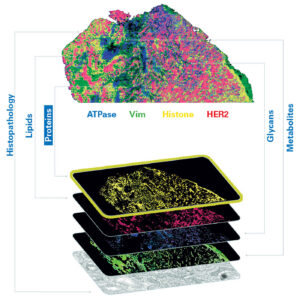

Mike Easterling, PhD, vice president of MALDI Imaging at Bruker Daltonics, stresses that he is interested in more than just RNA and proteins.

“We often hear multi-omics defined as transcriptomics and proteomics. That leaves critical biochemical layers unexplored, and this is where mass spectrometry contributes. We integrate metabolomics, glycomics, and lipidomics because these molecular classes are responsible for disease mechanisms that transcriptomics alone cannot capture.”

“Say you need to co-localize five transcripts, seven proteins, and several glycans and lipids within the same tissue region, organized by their spatial relationship to one another. That multi-omic biomarker composite may define a disease state much more precisely than any single layer. Our platforms support exactly that kind of investigation.”

Bruker uses matrix-assisted laser desorption/ionization (MALDI) mass spectrometry as the foundation of its multi-omics approach.

“Mass spectrometry is inherently multiplexed in a way that antibody-based approaches aren’t. A single acquisition can simultaneously detect hundreds of lipid species, glycans, and metabolites across a tissue section without the need for target-specific labels. That is a fundamental advantage for unbiased discovery.”

Easterling recounts a collaboration with Stanford University and the Medical University of South Carolina to spatially localize glycans in different tissues. This information was then combined with spatial transcriptomics and proteomics layers to analyze gliomas, a lethal cancer with very limited treatment options. Ultimately, the glycomics information emerged as the strongest classifier of tumor grade across all three omics layers.